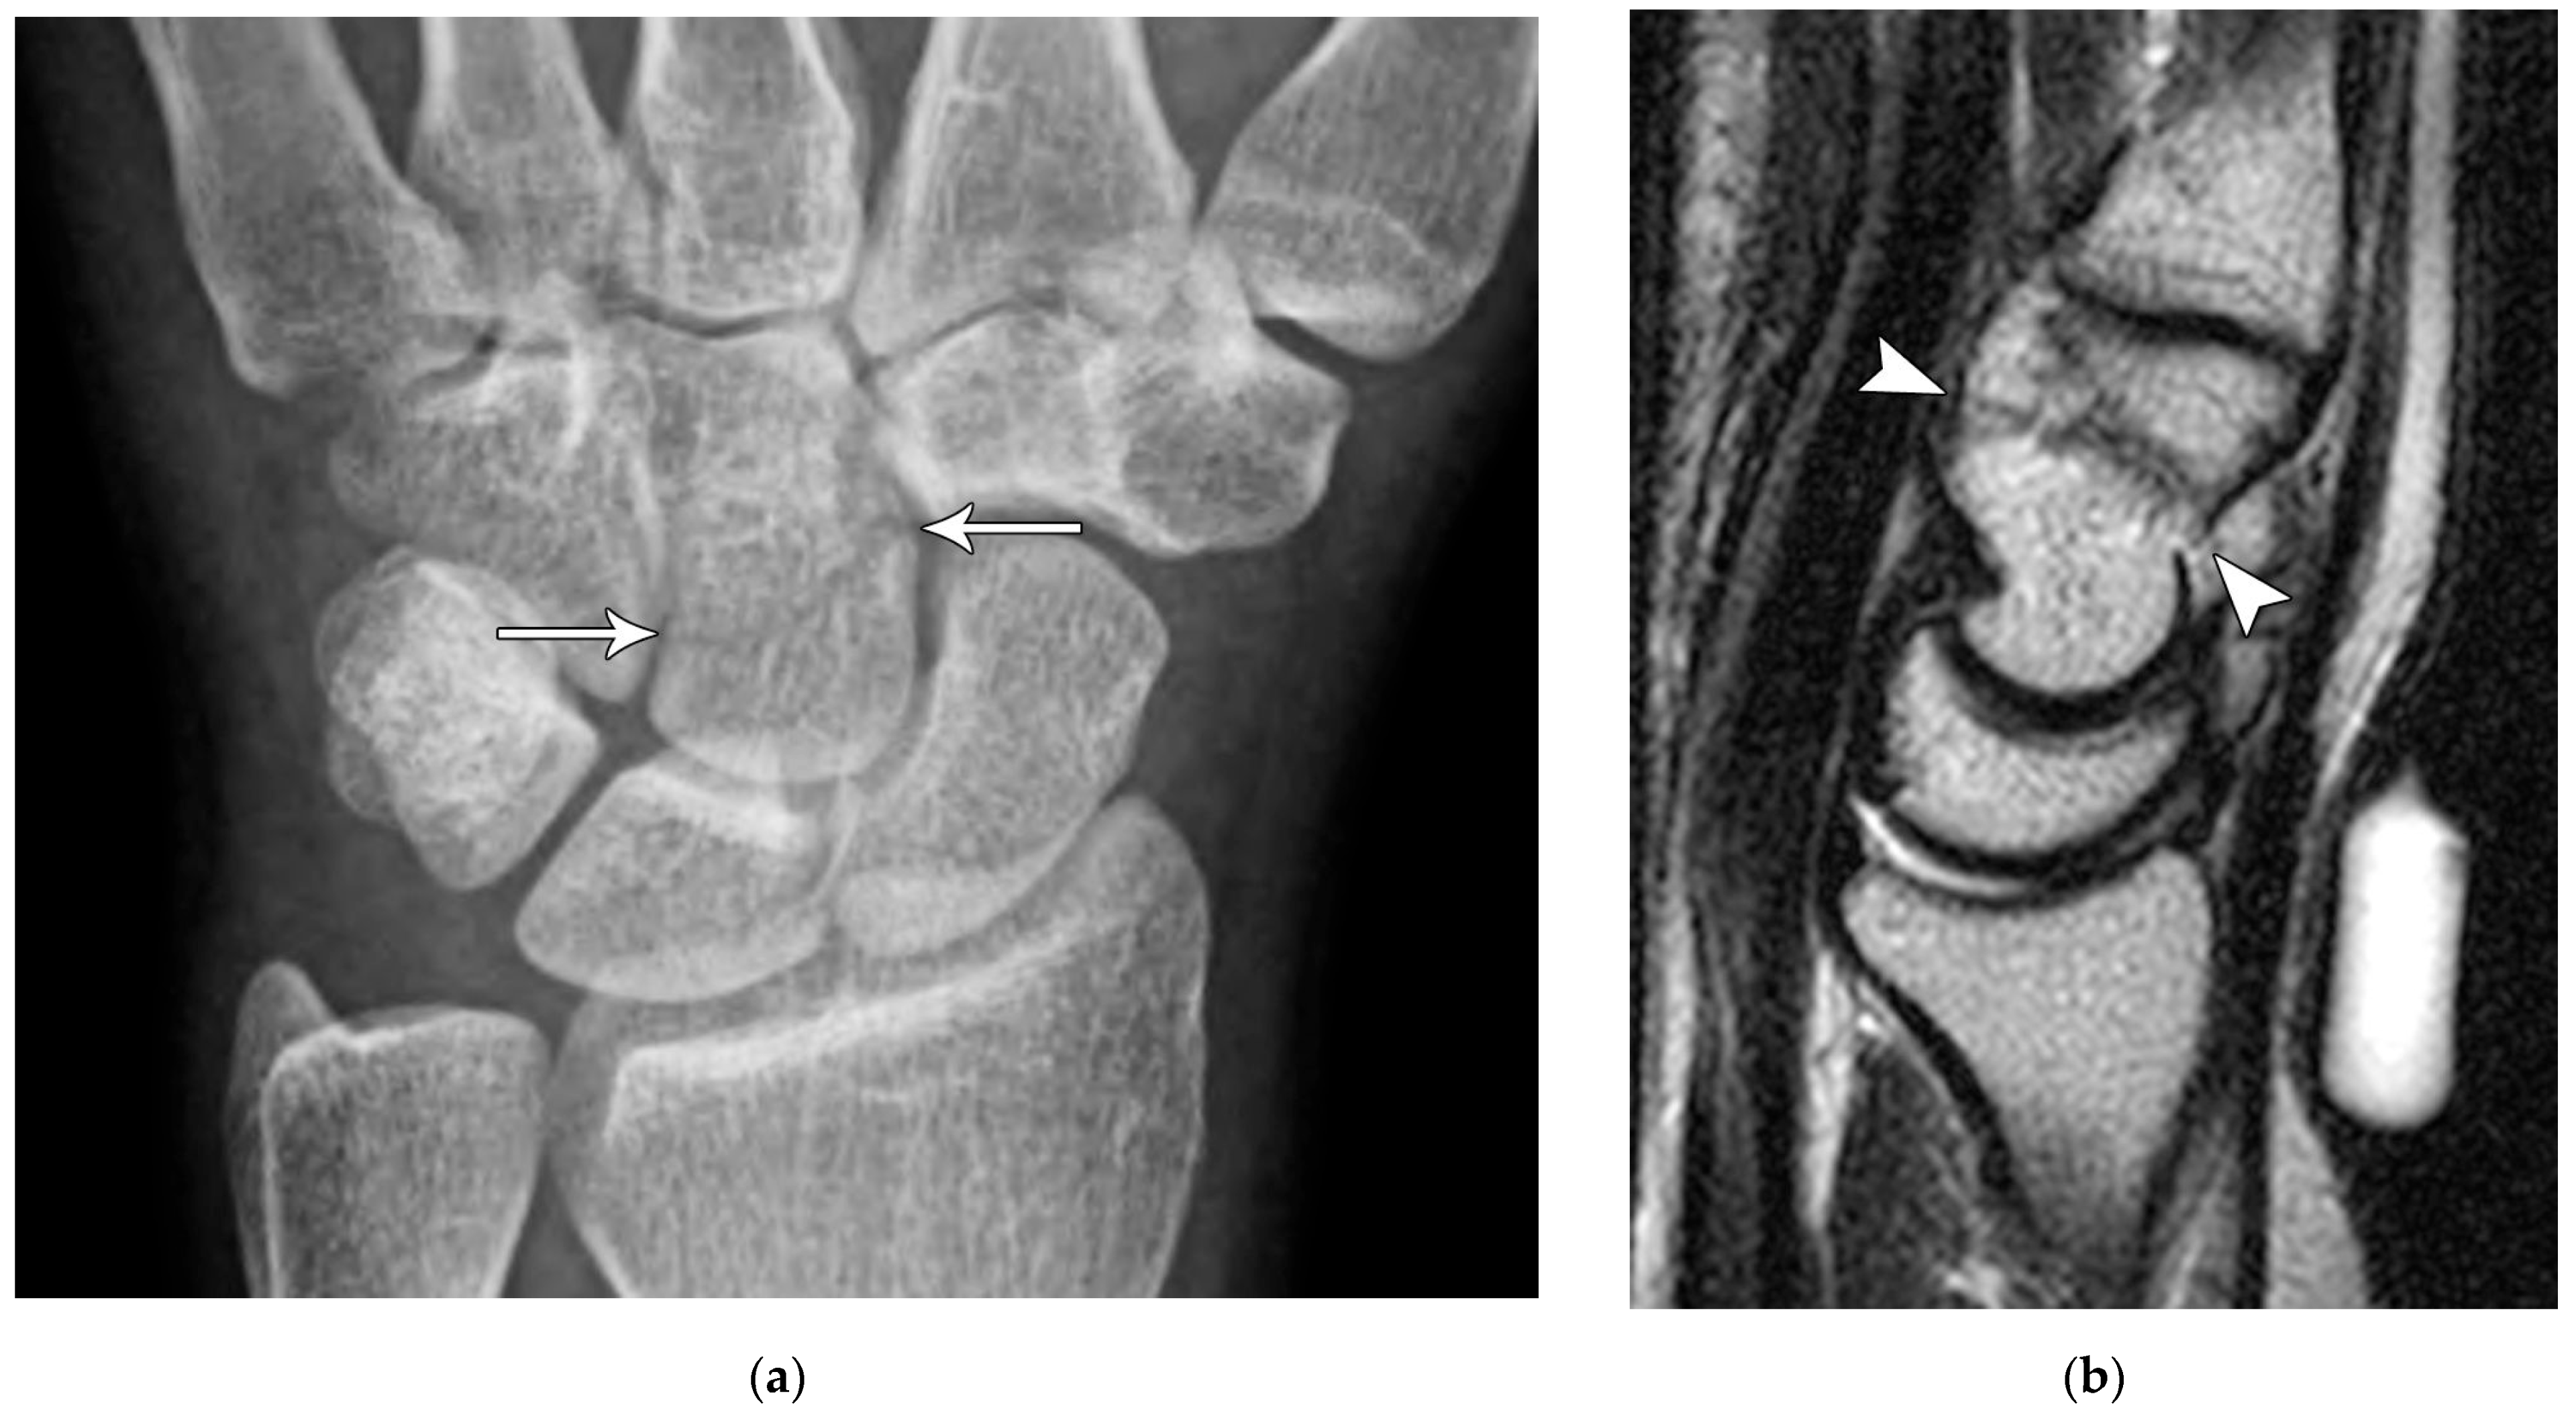

Figure 5. (a) PA radiograph showing marked sclerosis (arrow) of the proximal pole of the scaphoid after a scaphoid fracture. (b) Coronal reformatted CT in a different patient showing sclerosis (arrow) of the proximal pole of the scaphoid after a scaphoid fracture, indicating osteonecrosis.